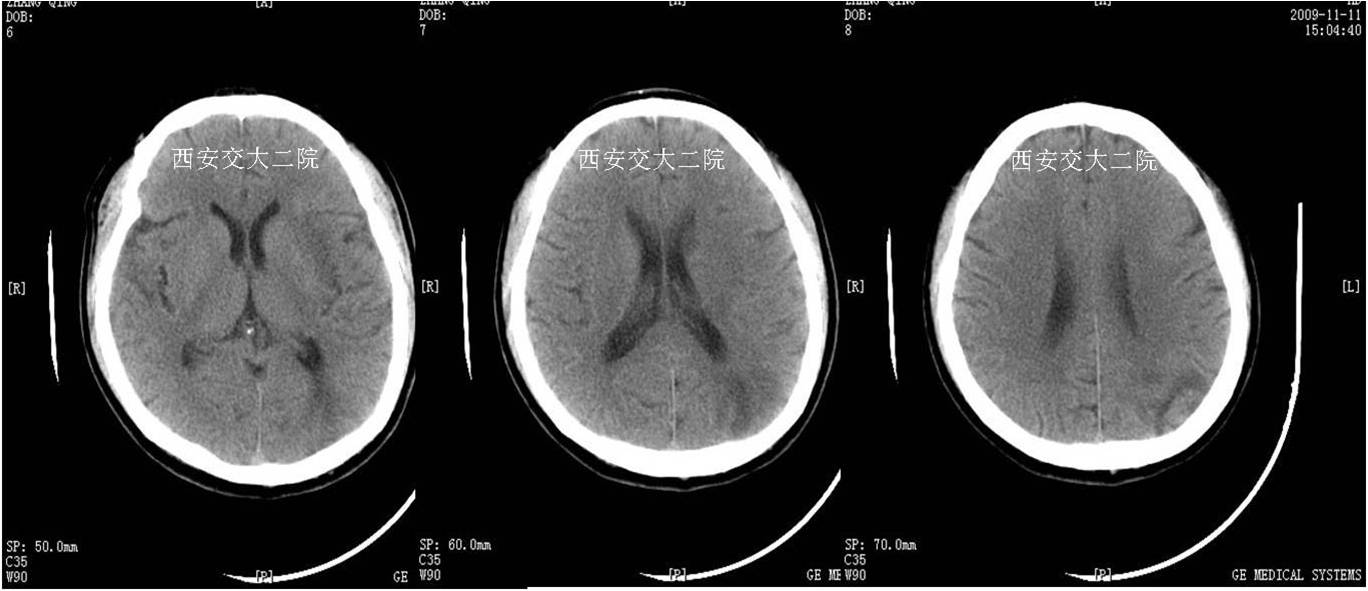

术前CT(病后1h)

术后24小时脑CT

急诊脑CT

取栓后即刻脑CT及临表

术后24h脑CT及临表

术后4天脑CT及临表

术后2周脑CT及临表